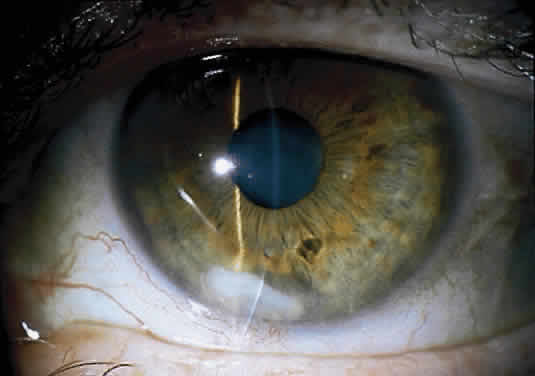

Clinically, the infected staphylococcal corneal ulcer presents with a yellow-white, well-demarcated area of infiltrate, which appears directly beneath an epithelial defect (Fig. 2). On occasion, multiple, small satellite lesions may develop. The infection may initially be superficial; however, if inadequately treated it can produce a mid to deep stromal abscess that may eventually lead to perforation. Stromal edema and white blood cell migration frequently surround the dense infiltrate and clear as the infection comes under control. Although there may be a marked anterior chamber reaction with hypopyon, the ulcer more frequently is indolent, with only a minimal inflammatory reaction.34